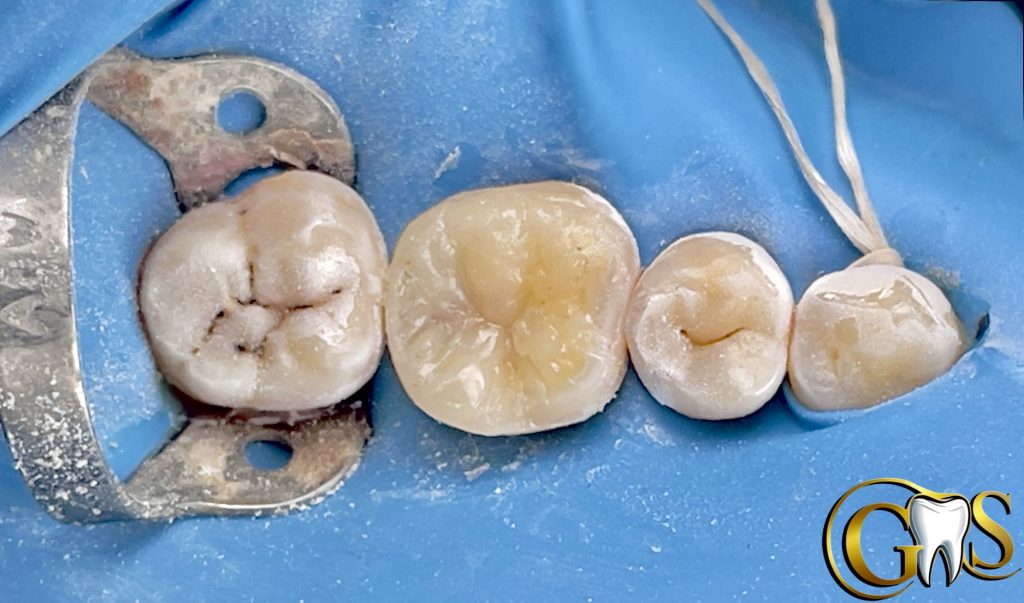

2-selective etching using charm etch (37%phosphoric Acid)

3-cotton Dampened in Chlorohexidine for MMps inhibition

4-IDS

5-Resin coating

7-Ever X posterior for Dentine replacement (mimic Dentine under stresses)

8-Brown stain